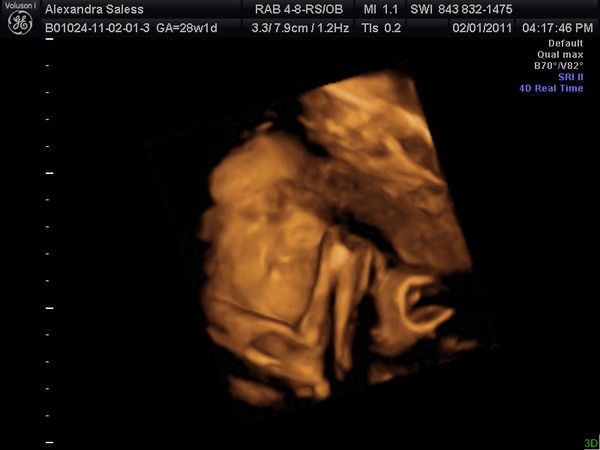

8W 4T Lexabailey's erstes US-Bild!

17.09.2010

20.14mm gross

Herzschlag 166 bpm

Man sieht noch den Dottersack und beim Arzt auf dem Ultraschallgeraet konnte man schon super die kleinen Ansaetze der Haende und Fuesse sehen, sieht man auf dem Bild hier leider nicht so gut.